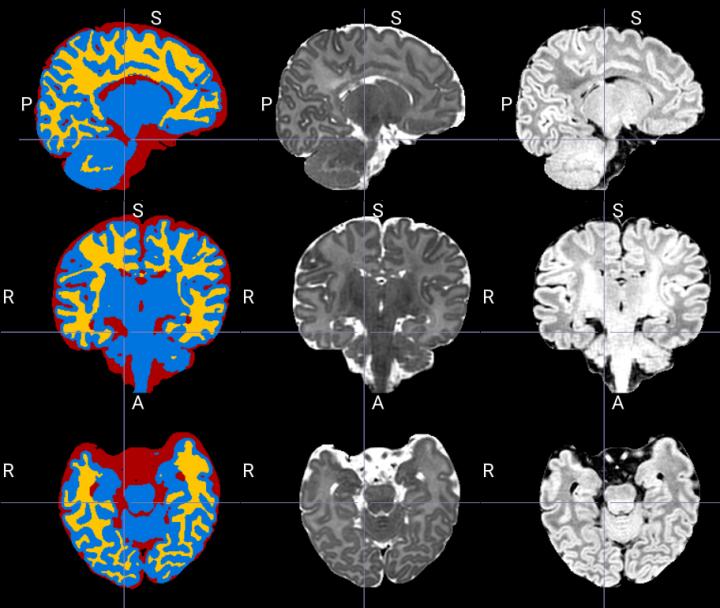

image: Example of segmentation produced by the tool which separates the structures in cerebrospinal fluid (red), grey matter (blue) and white matter (yellow) from MRI images T2 (middle column) and T1 (right column).

"This is one of the first times that artificial intelligence has been used to better define the different parts of a newborn's brain on an MRI: namely the grey matter, white matter and cerebrospinal fluid," said Dr. Gregory A. Lodygensky, a neonatologist at CHU Sainte-Justine and professor at Université de Montréal.

In evaluating a range of tools available in artificial intelligence, CHU Sainte-Justine researchers found that these tools had limitations, particularly with respect to pediatric research. Today's neuroimaging analysis programs are primarily designed to work on "adult" MRIs. The cerebral immaturity of newborns, with an inversion of the contrasts between grey matter and white matter, complicates such analyses.

Inspired by Dolz's most recent work, the researchers proposed an artificial neural network that learns how to efficiently combine information from several MRI sequences. This methodology made it possible to better define the different parts of the brain in the newborn automatically and to establish a new benchmark for this problem.